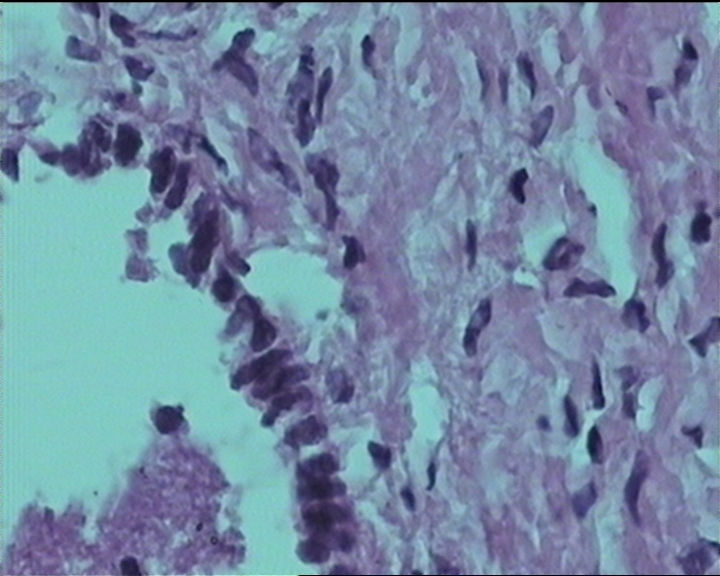

54岁女性,临床“宫颈息肉”送检;巨检:组织一块1。5*1CM,灰红。

输卵管粘膜化生

It is benign. Benign endocervical polyp with tubal metaplasia.

细胞及腺体均有异形,图6、11、16象有纤维间质反应,考虑高级别上皮内瘤变/原位癌,腺癌不能除外。

Sternberg病理学上诊断宫颈原位腺癌的标准是腺体的上皮去粘液分化,呈乳头状或筛网状增生,核分裂易见,这例显然达不到此标准。此例还是归入到腺上皮不典型增生为好。

杨老师说它是良性的,是个颈管内膜息肉伴输卵管上皮化生,良性